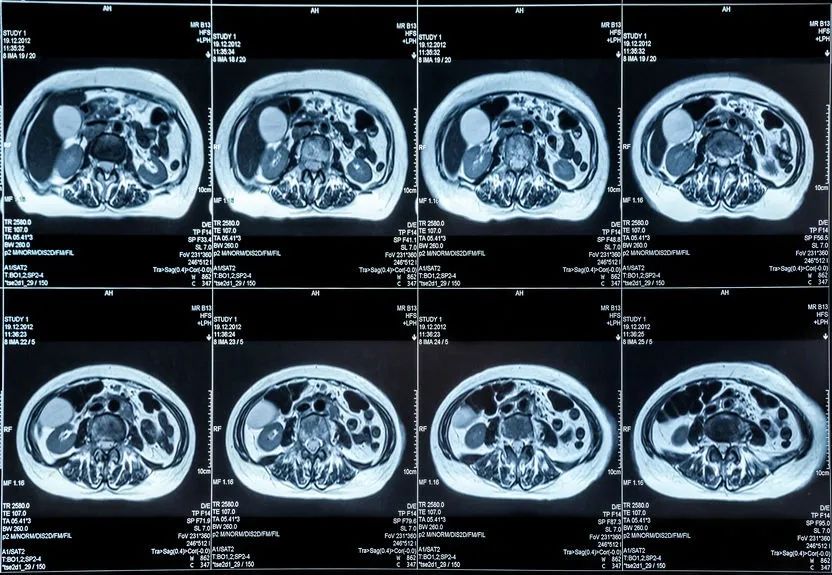

核磁共振:摇一摇再看

常用于头部、腹部和脊柱。

价格相对较高。原理是:利用强大的磁场,让身体中的水分振动起来,再平静下来,感受里面的振动,形成像后可以观察到正常组织与患病部位之间的差异。

所以,核磁共振也被戏说为“摇摇看的检查”。

核磁共振可以检查的部位很多,包括脑部、血管、肌肉、韧带、脊柱等等,但是建议在有症状或医生建议下做磁共振检查,正常的体检作为疾病的初期筛查,通常没有必要做核磁共振。

颈椎病、腰椎间盘突出等椎间盘疾病需要观察椎间盘与相应的神经根,要想更好观察这些软组织,最优选择就是核磁。同样,对于关节、肌肉、脂肪组织检查,核磁也是首选。

核磁共振因为名字里带个“核”字,大家总是误解它可能有放射线和辐射,其实这个“核”指的是氢原子核,不是什么“核弹”。磁共振就是人为地制造一个磁场,利用电磁波信号成像,没有放射线,对人体没有辐射也没有伤害。